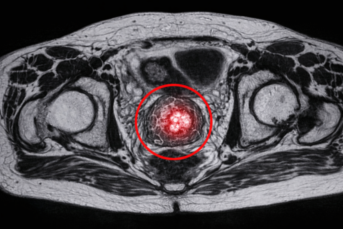

3. Bildgebung: Meist eine spezielle Magnetresonanztomographie (MRT) der Prostata.